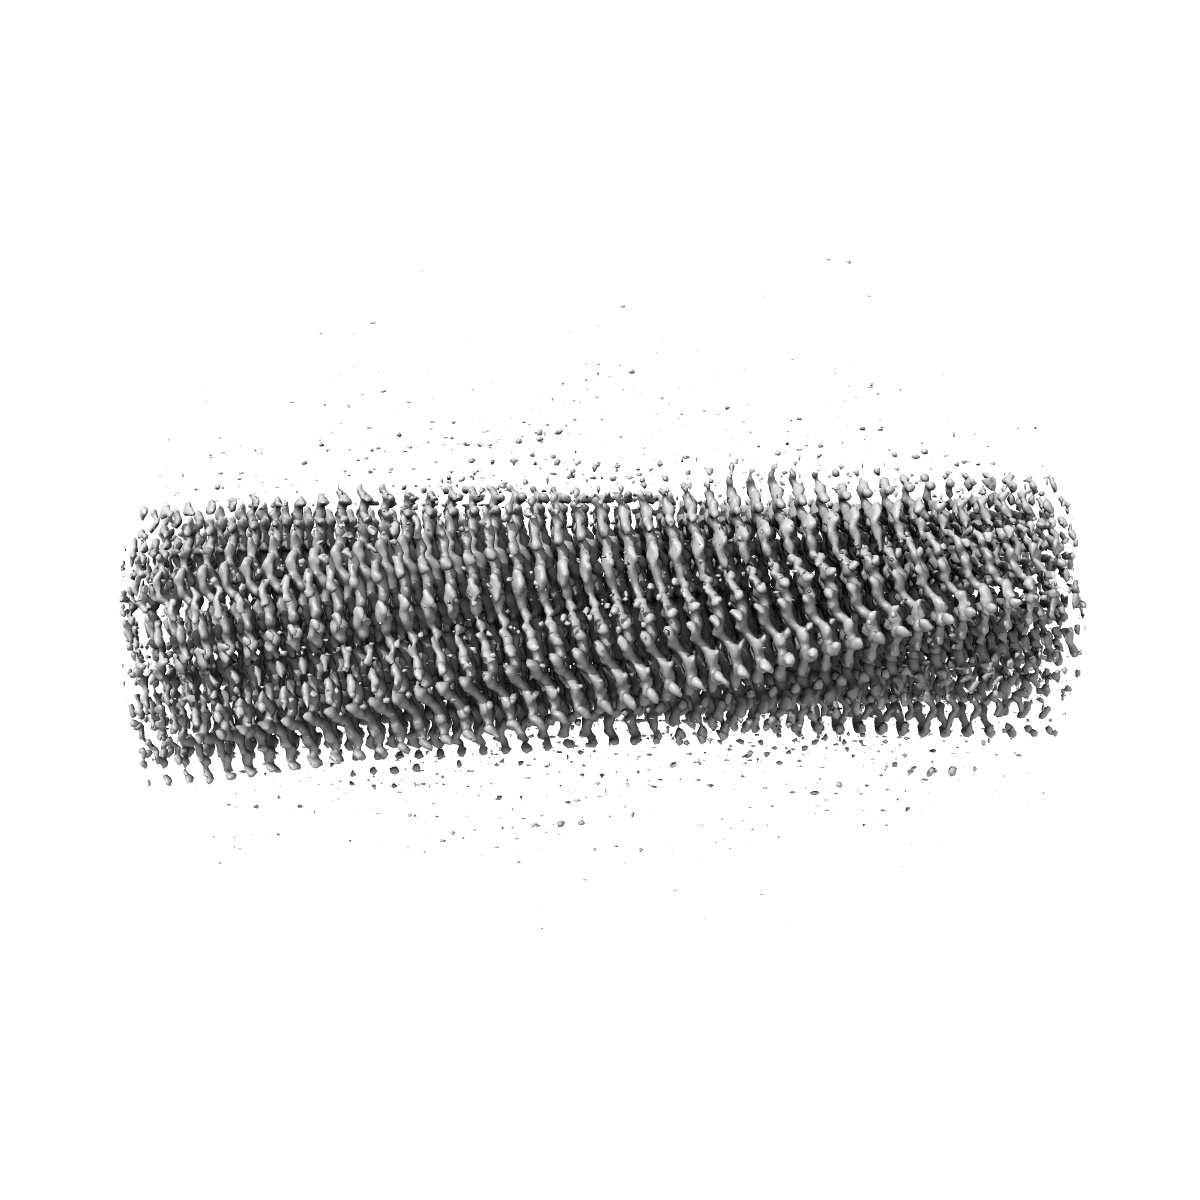

Structure of heteromeric amyloid filament of TDP-43 and AXNA11 from FTLD-TDP Type C (variant 2)

Helical reconstruction2.9 Å

Sample: heteromeric amyloid filament of TDP-43 and AXNA11 from FTLD-TDP Type C (variant 1)

Heteromeric amyloid filaments of ANXA11 and TDP-43 in FTLD-TDP Type C.

- Arseni D, Nonaka T, Jacobsen MH, Murzin AG, Cracco L, Peak-Chew SY, Garringer HJ, Kawakami I, Suzuki H, Onaya M, Saito Y, Murayama S, Geula C, Vidal R, Newell KL, Mesulam M, Ghetti B, Hasegawa M & Ryskeldi-Falcon B. (2024) Heteromeric amyloid filaments of ANXA11 and TDP-43 in FTLD-TDP Type C. Nature,